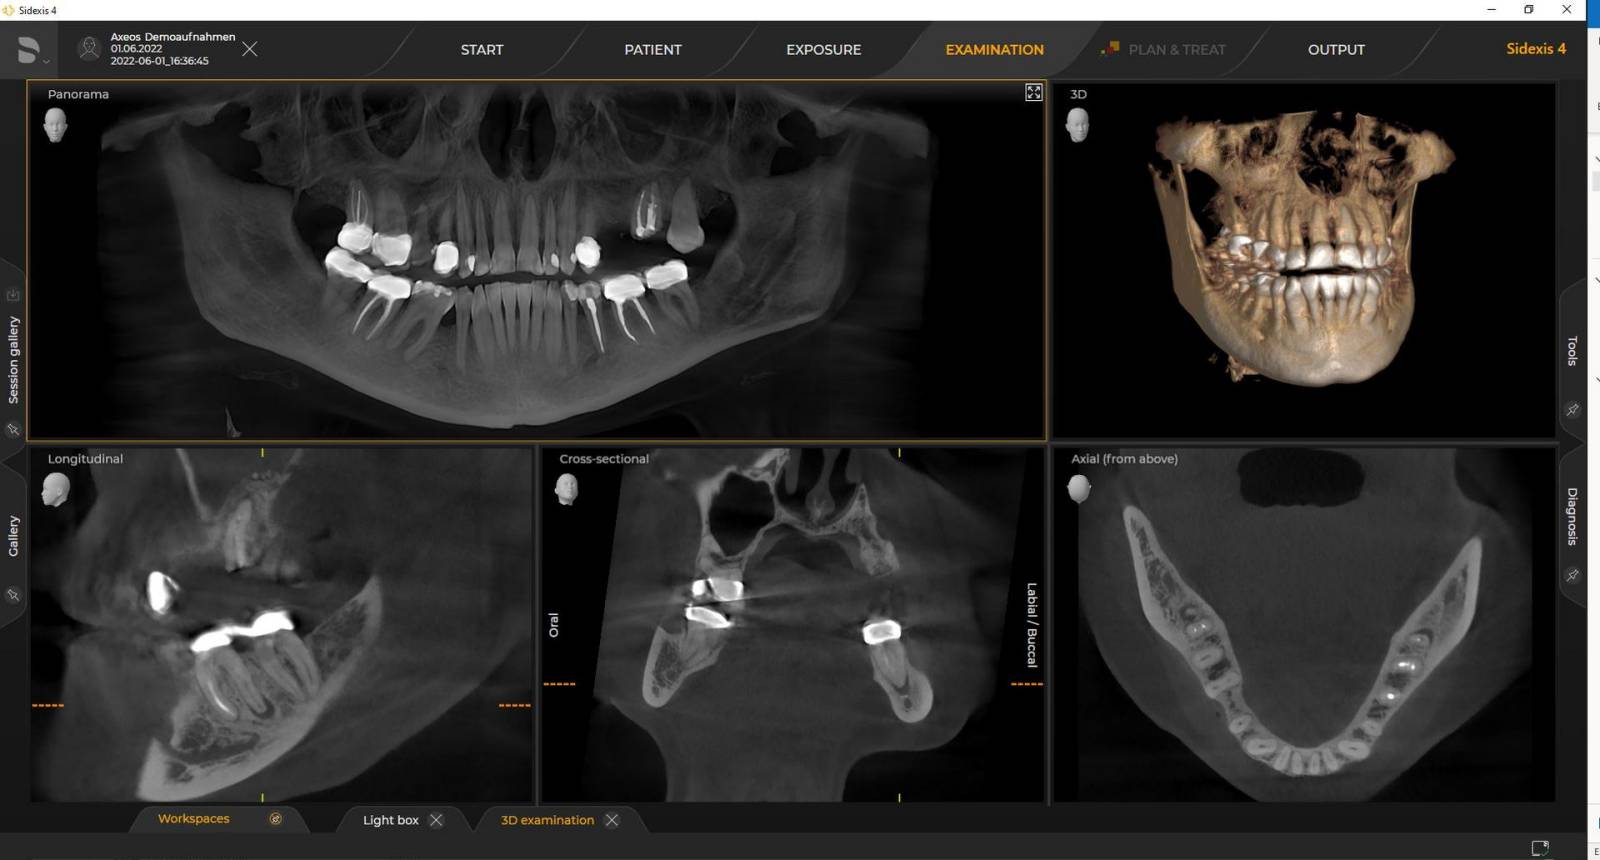

Axeos: l’unità 2D/3D più versatile con un ampio campo visivo e un’eccezionale qualità dell’immagine per studi con un ampio spettro di trattamenti. Sviluppato insieme a dentisti e medici, Axeos offre la gamma più completa di funzioni tra tutti i dispositivi radiografici extraorali Dentsply Sirona. Oltre all’eccellente qualità dell’immagine e alle dimensioni del volume 3D personalizzabile, il dispositivo radiografico dentale è completamente ottimizzato per un maggiore comfort del paziente. Axeos non solo offre qualità in termini di prestazioni e comfort, ma grazie all’armadietto per accessori integrato e alla luce ambientale ha anche un design pluripremiato.

I requisiti seguono quelli dei software di elaborazione delle immagini Sidexis 4 e Axeos. Per ulteriori dettagli, consulta i requisiti di sistema di Sidexis 4 e i requisiti di installazione di Axeos.

I dispositivi radiografici 3D Dentsply Sirona funzionano esclusivamente con Sidexis 4. Tuttavia, la migrazione dei dati da Sidexis XG a Sidexis 4 è molto semplice. Sidexis 4 offre l’esperienza digitale completa con gli strumenti più recenti.